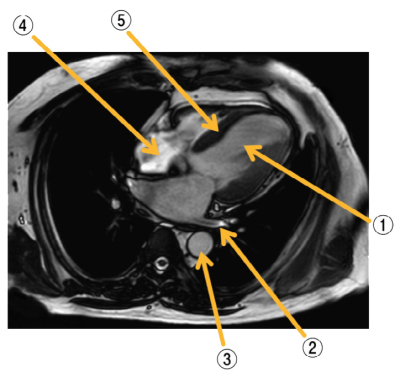

正常な成人男性の胸部MRIを別に示す。図に示す部位と名称の組合せで誤っているのはどれか。

a. ① ー左心室

b. ② ー肺動脈

c. ③ ー下行大動脈

d. ④ ー右心房

e. ⑤ ー心室中隔

②は肺静脈です。左心房に流入しているので。